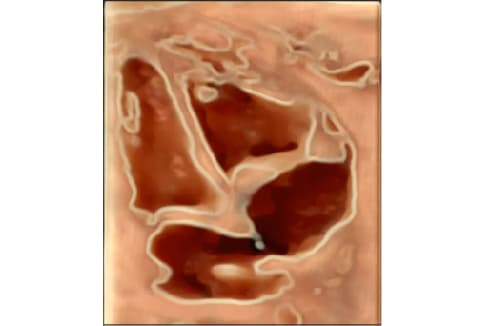

- 4D STIC Fetal echocardiography and Fetal Quantification ( fetal HQ analysis)

- Most advanced technology- including Voluson Expert 22 Ultrasound equipment with its full array of transducers and fetal HQ software- for fetal heart function assessment.

- Accurate diagnosis of fetal heart defects through real-time and offline analysis of fetal heart function evaluations.